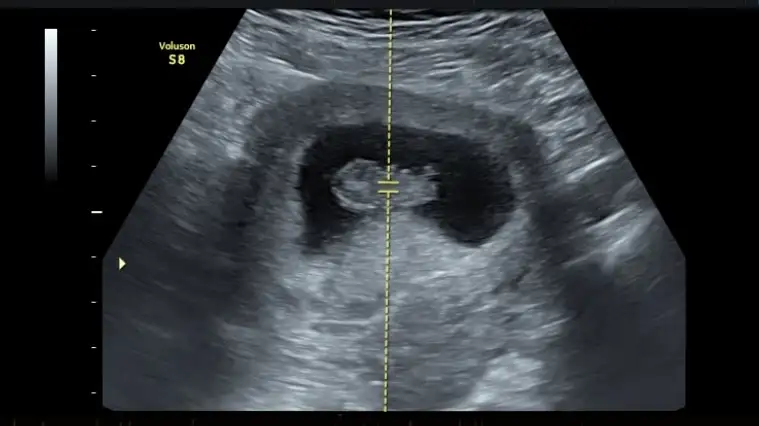

Ben 9. haftadaki ultrasonumu tekrar atayım ya meraktan deliriyorum cinsiyet tahmini yardııım lütfen

Ben kıza benzettim ama nub teorisi tutmayan bir sürü kişi var doktorun o anda çektiği açı çok önemli. Mesala ben dün doktora gittim ve bebeğin nubu bazen kalkık bazen de paraleldi. Allah gönlüne göre versin hayırlı evlat olsun.